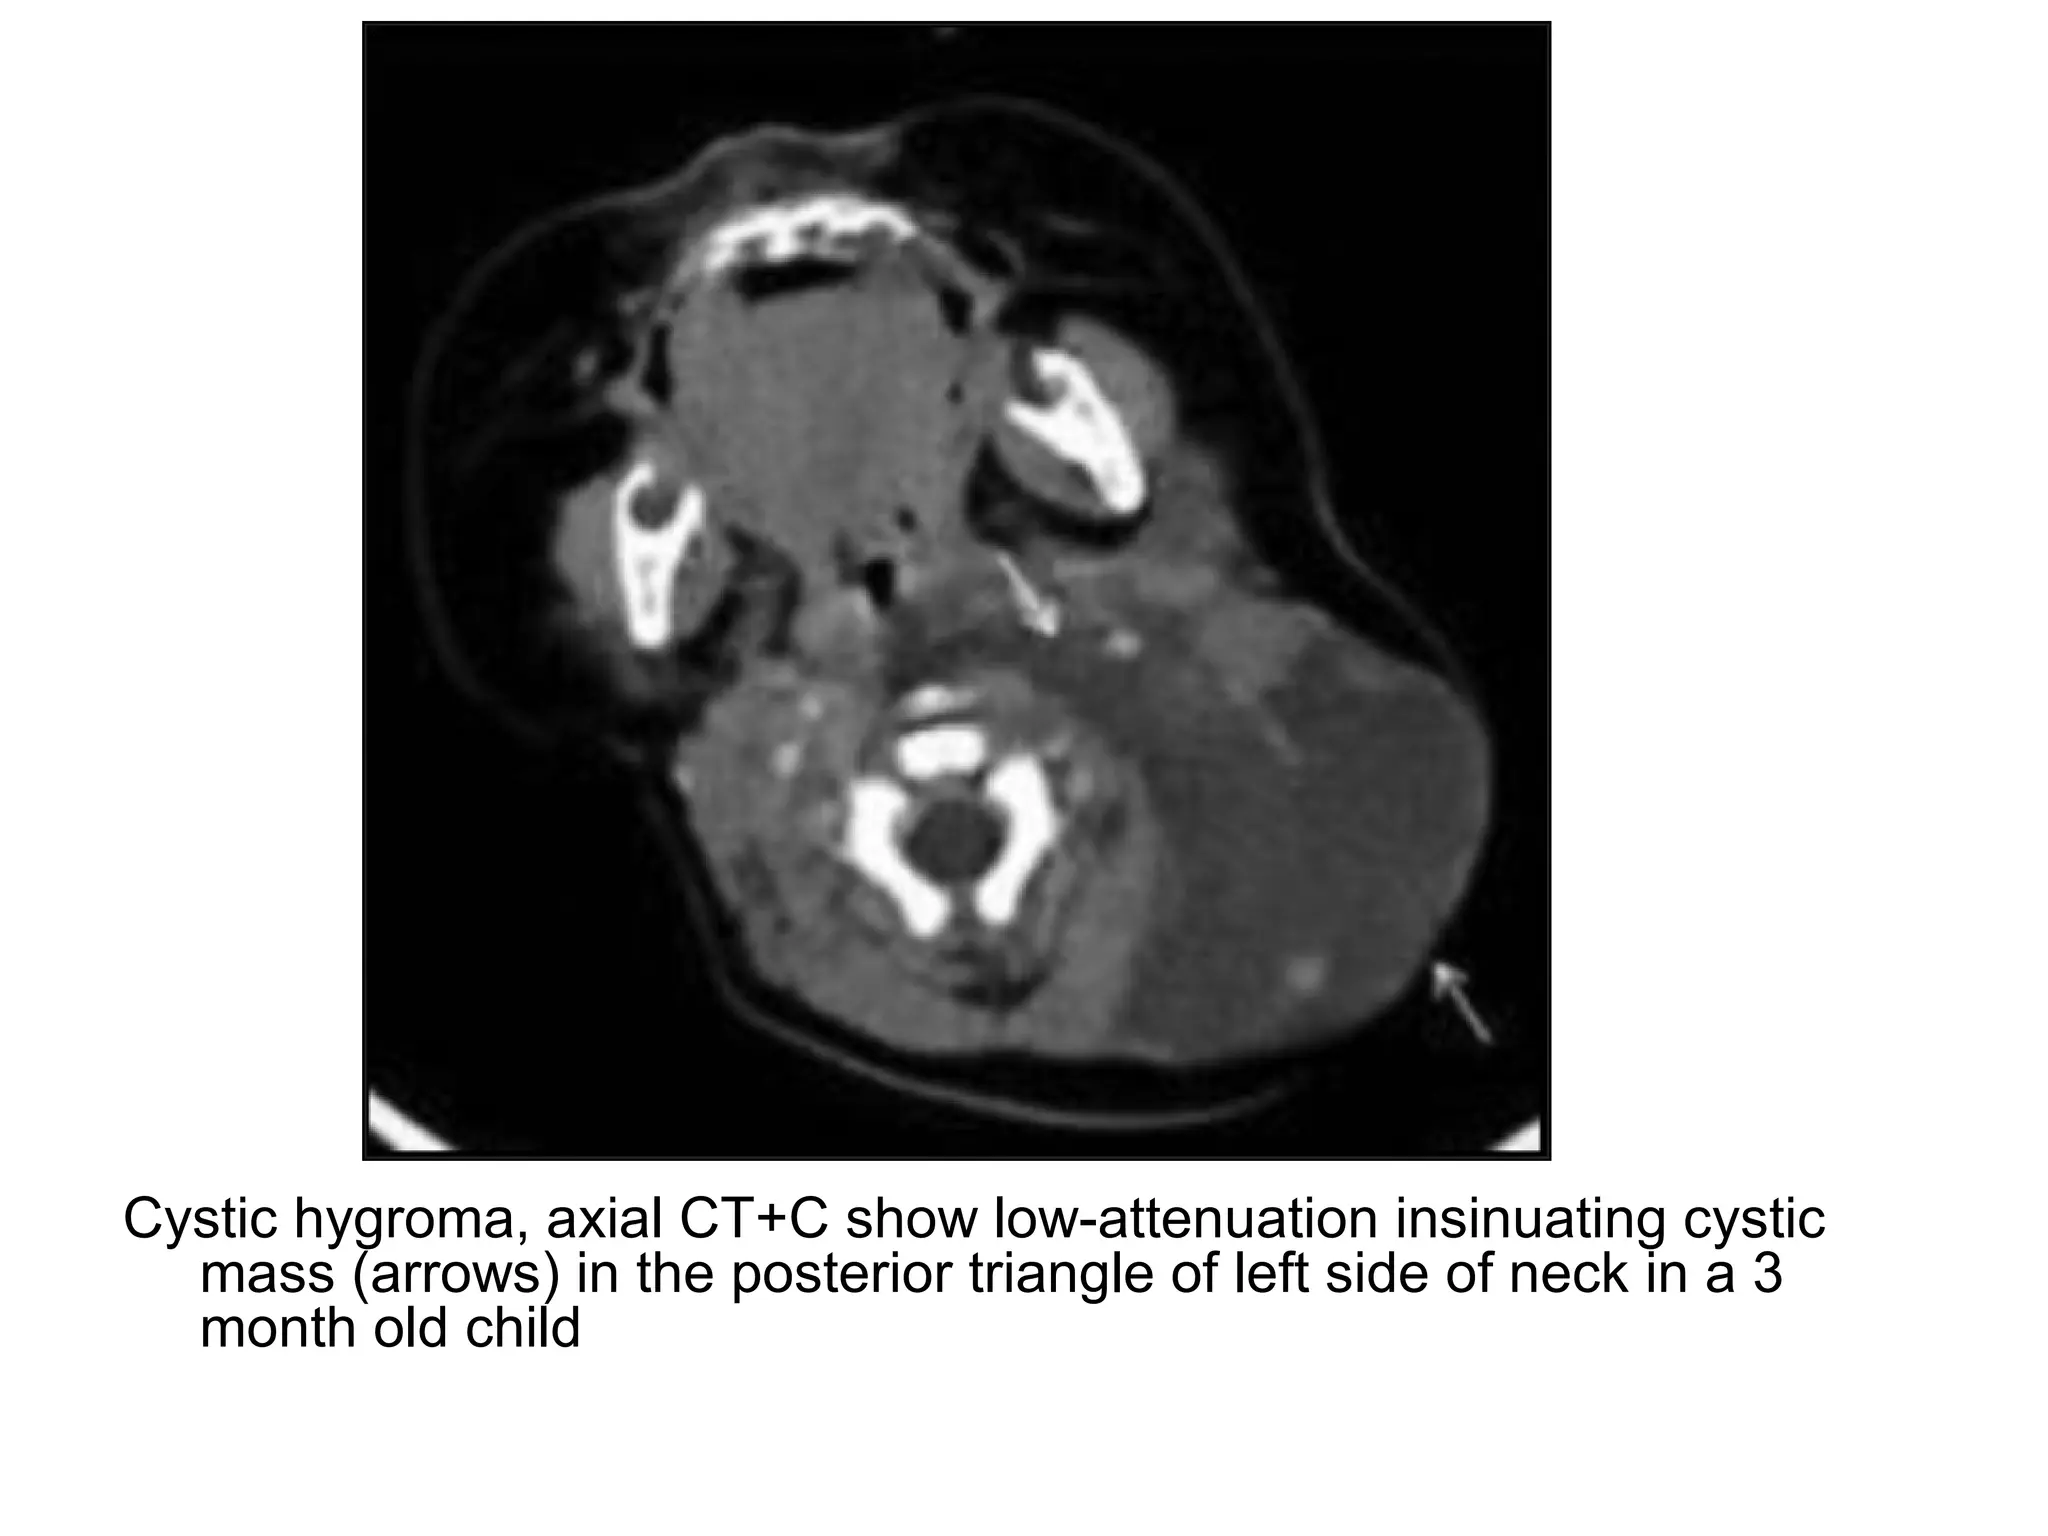

Cystic hygroma, axial CT+C show low-attenuation insinuating cystic

mass (arrows) in the posterior triangle of left side of neck in a 3

month old child

4-Posterior Cervical Space: -Contents : 1-Fat 2-Cranial nerve XI (schwannoma, neurofibroma) 3-Brachial plexus : -Schwannoma, neurofibroma -Direct invasion of apical lung (Pancoast tumor), breast carcinoma & lymphoma 4-Primitive Embryonic Lymph sacs (Cystic hygroma) 5-Lymph nodes (Lymphoma, metastases, TB)

Cystic hygroma, axialCT+C show low-attenuation insinuating cystic mass (arrows) in the posterior triangle of left side of neck in a 3 month old child